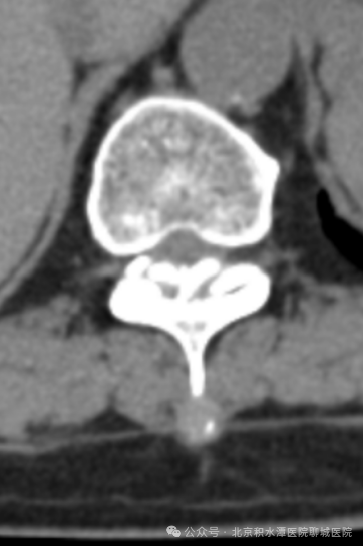

术前影像:T11/12胸椎黄韧带骨化,胸椎椎管狭窄

术后影像:去除少量骨质扩大胸椎椎管

并取出骨化的黄韧带